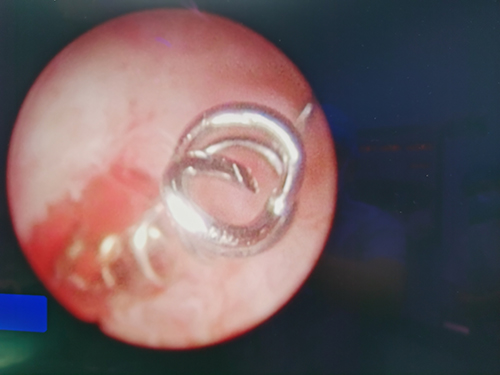

随后,患者在麻醉下行宫腔镜节育器取出术,置入30°检查镜检查,宫颈管光滑,宫腔呈桶状,节育环位于宫腔中下段,部分嵌钝于子宫层,取物钳钳夹节育环断端,宫腔检查镜后退随之取出宫内残留节育器。搔刮宫腔及两侧宫角,刮出组织标本送常规病理检查。